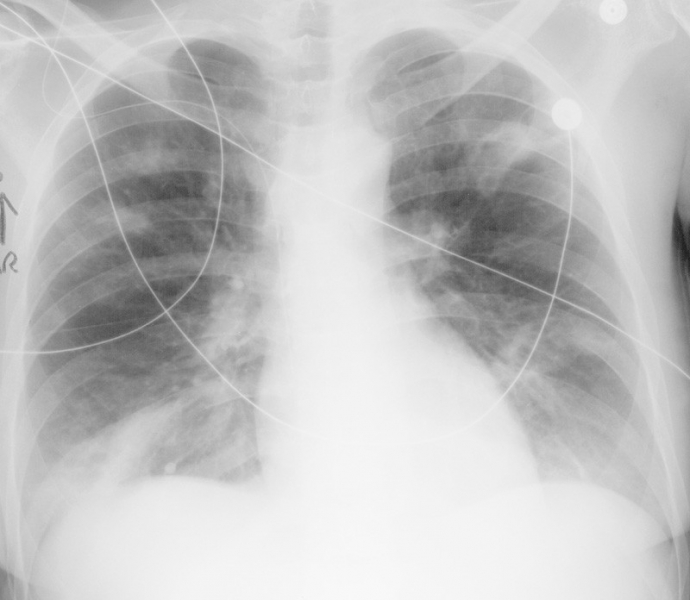

Blunt Cardiac Injury Blunt thoracic trauma carries approximately a 20% risk of BCI, but the setting of chamber or septal injury.15 Aortic valve injury is considered to be most common, and may result from sudden increase in intrathoracic pressure against ... Retrieve Doc

Blunt Cardiac Injury - Emed.theclinics.com